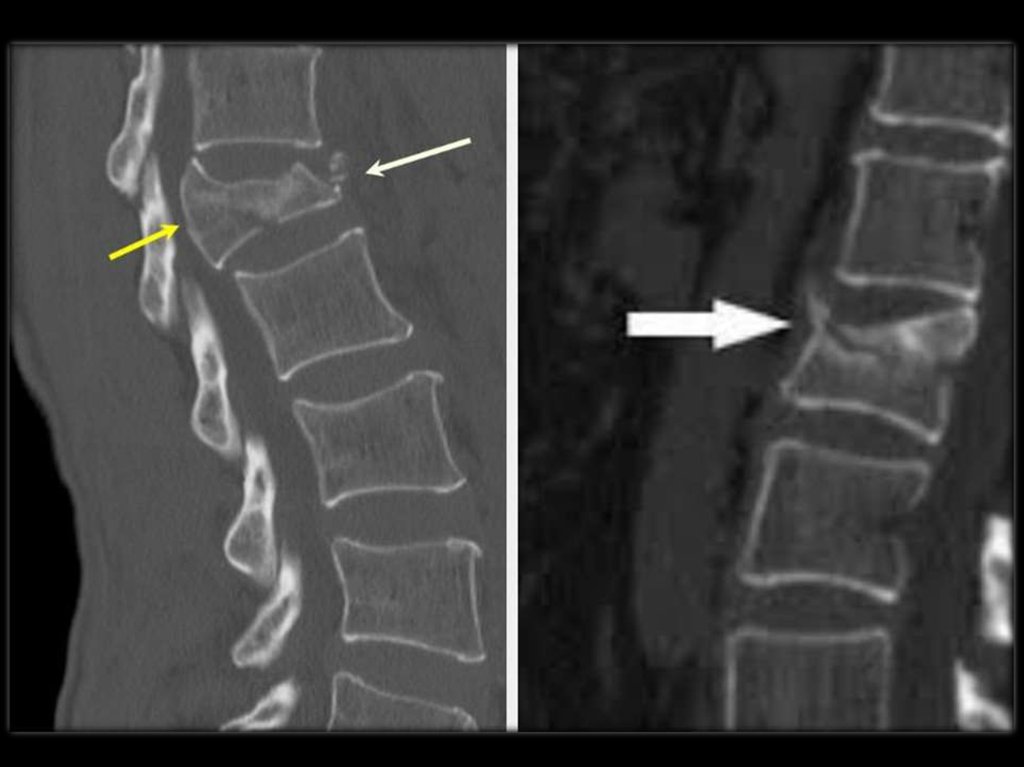

R-признаки при ОП (R-графия позвонков в

боковой проекции), потеря костной массы

при этом составляет 20 – 30%.

разряжение губчатой кости;

уменьшение количества трабекул на

единицу плотности кости;

повышенная прозрачность тел позвонков;

видны вертикальные трабекулы;

“рамочная” структура

тел

позвонков

(истончение и резкая подчёркнутость

контуров кортикального слоя кости при

разряжении

плотности

кости

тела

позвонка);

деформация тел позвонков

Виды деформации тел позвонков:

передняя клиновидная;

задняя клиновидная;

двояковогнутая деформация (по типу

“рыбьих”);

компрессионная деформация;

сочетанная.